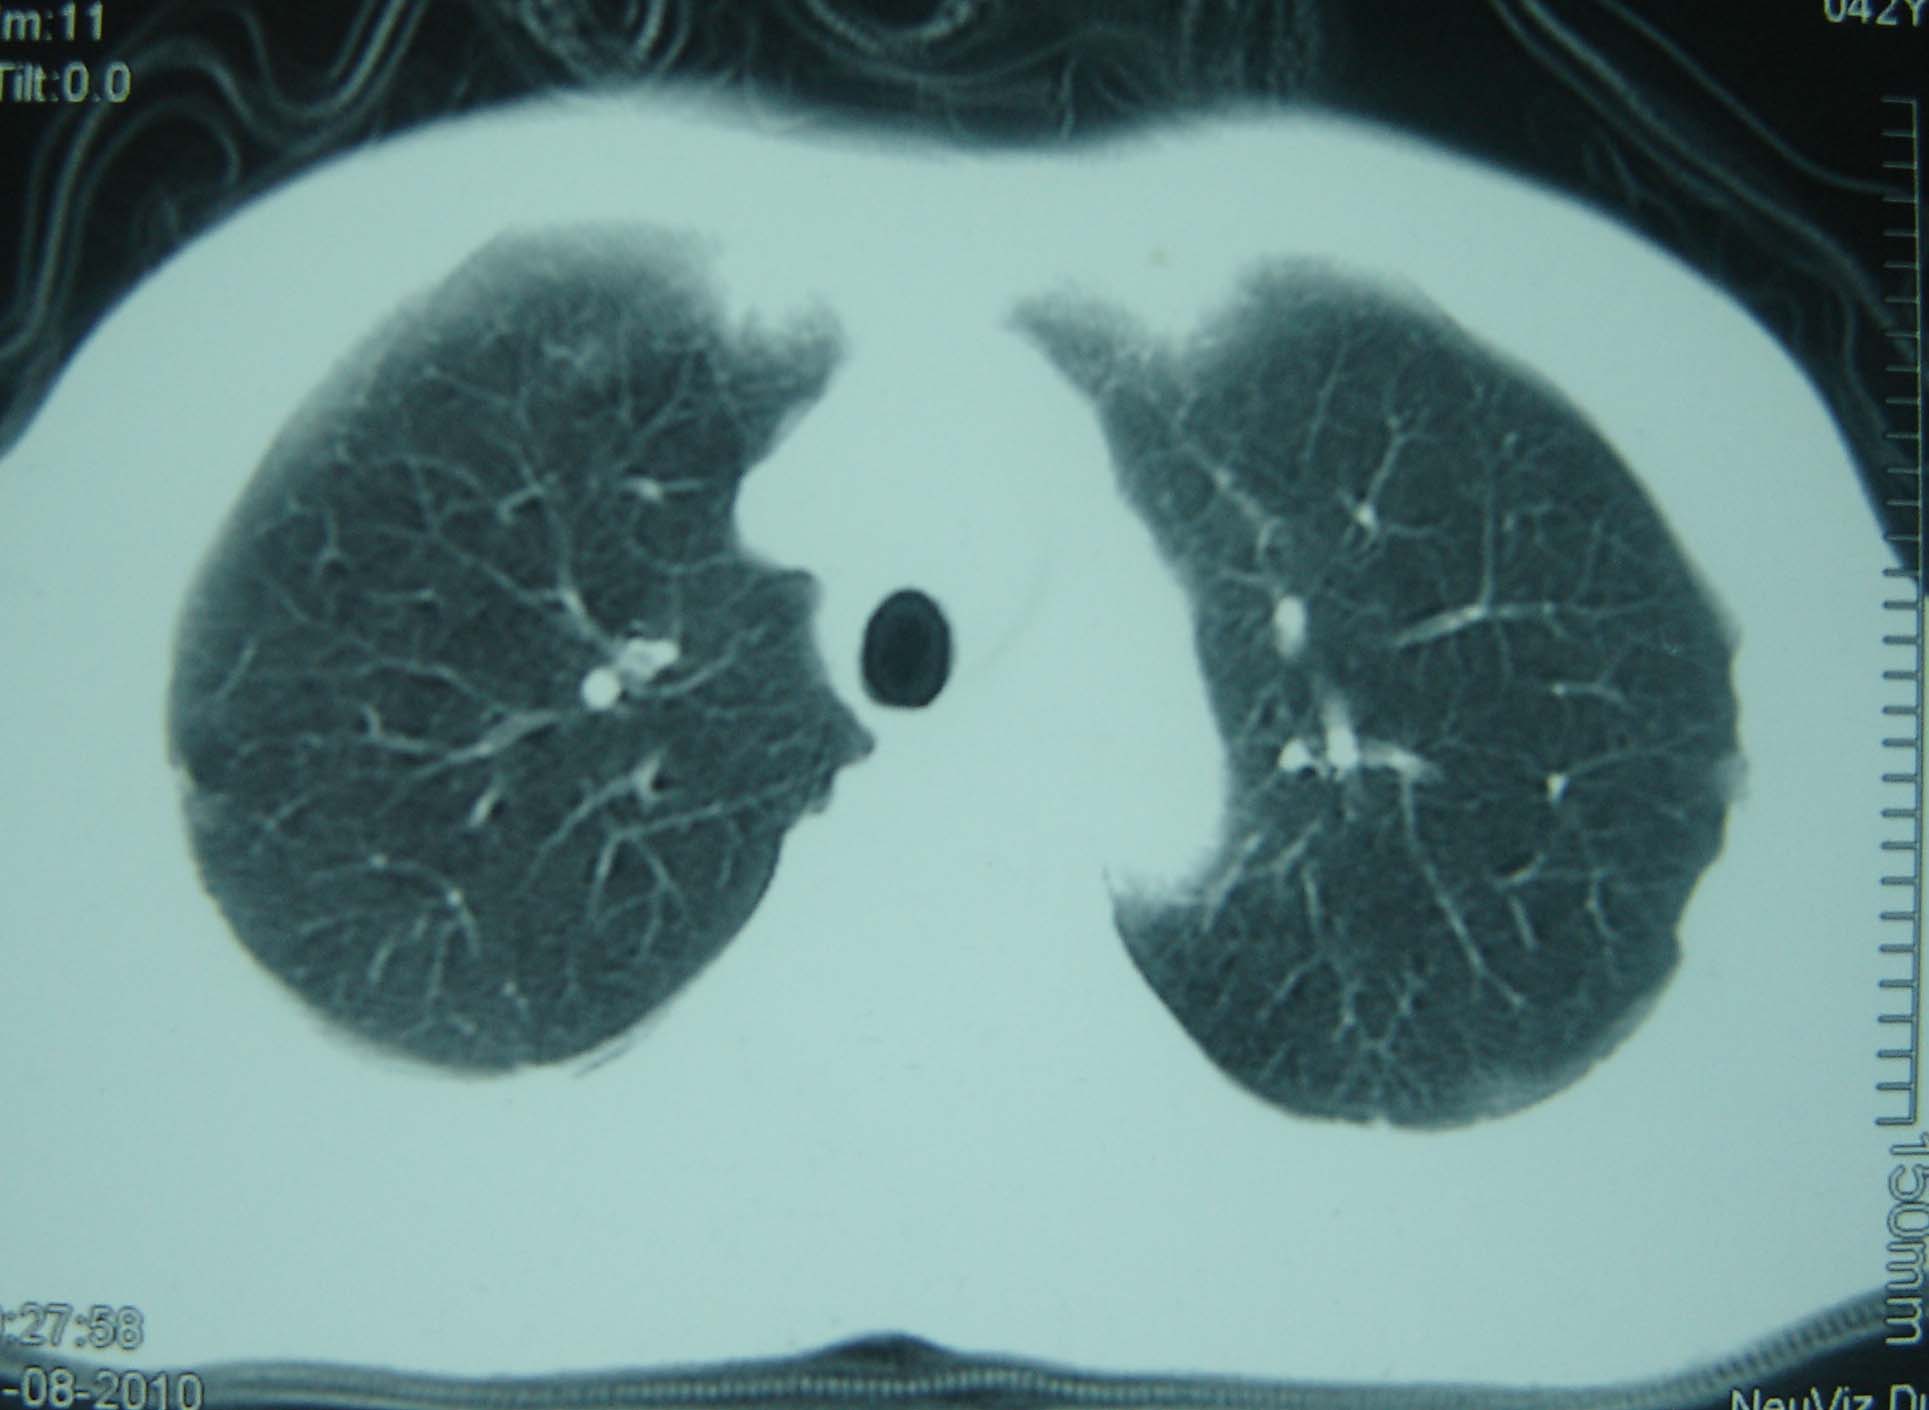

标题: CT25321:两肺多发结节 请会诊 [打印本页]

男 、43岁,咳嗽胸痛,装修工,平时接触粉尘较多,有吸烟史10多年,纤维支气管镜检查未发现异常,胃镜、腹部b超检查亦未发现异常,颈部淋巴结活检未发现肿瘤细胞。